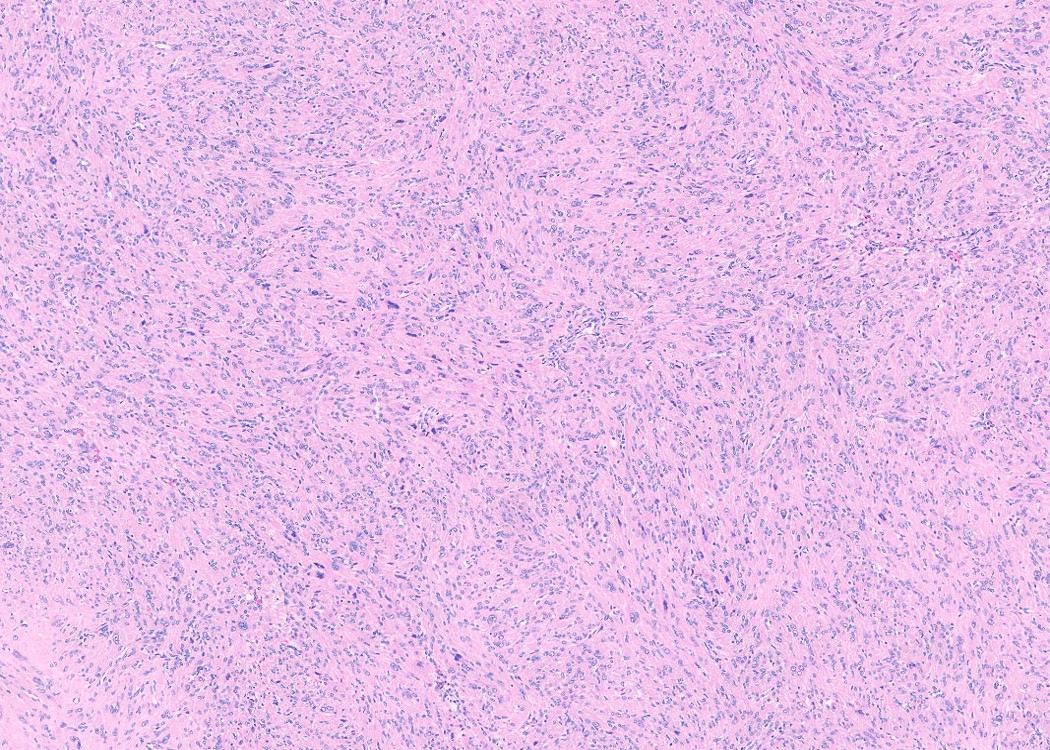

Microscopic (histologic) description

- Subtypes:

- Cellular

- Increased cellularity (more cellular than background myometrium)

- Scant cytoplasm without increased mitotic activity and atypia

- May have irregular borders

- Highly cellular leiomyoma is not a WHO diagnosis

- Cellular

Contributed by Sabrina Croce, M.D., Ph.D., Kristina Doytcheva, M.D., Jennifer A. Bennett, M.D. (Case #508) and @Andrew_Fltv on Twitter